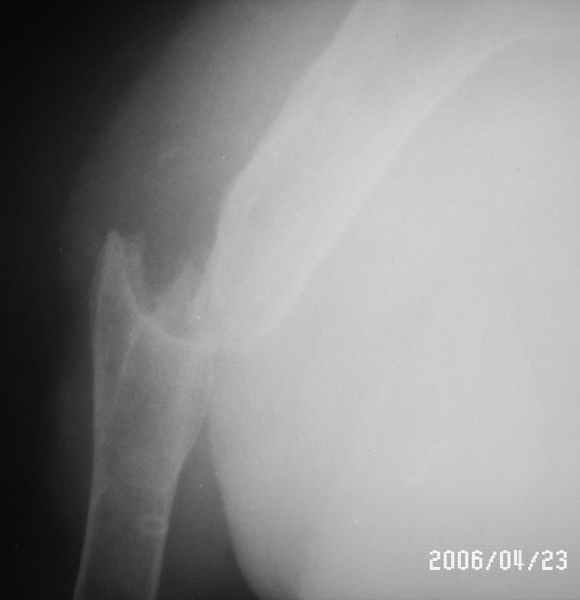

Уважаемые коллеги! Помогите в выборе тактики лечения больной Р.,56 лет, с болтающимся ложным суставом с/3 правой плечевой кости 2-х летней давности. В анамнезе - бронхиальная астма, гормонозависимая форма, ожирение III cт. Травма - автодорожная, получила закрытый многооскольчатый перелом диафиза плечевой кости со смещением (от метафиза до метафиза), в экстренном порядке нами произведен закрытый остеосинтез стержневым аппаратом, отломки удалось сопоставить анатомически. В дальнейшем больная выпала из поля зрения. Как потом выяснилось, после снятия стержневого аппарата, больная долечивалась по Илизарову специалистом из г. Кургана. Аппарат Илизарова удален из-за нагноения мягких тканей. Последние два года работая бухгалтером, фиксирует плечо ортезом. Теперь вновь обратилась к нам для ликвидации ложного сустава.